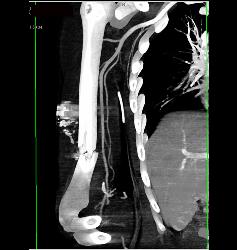

Abdominal Wall Hematoma S/p MVA